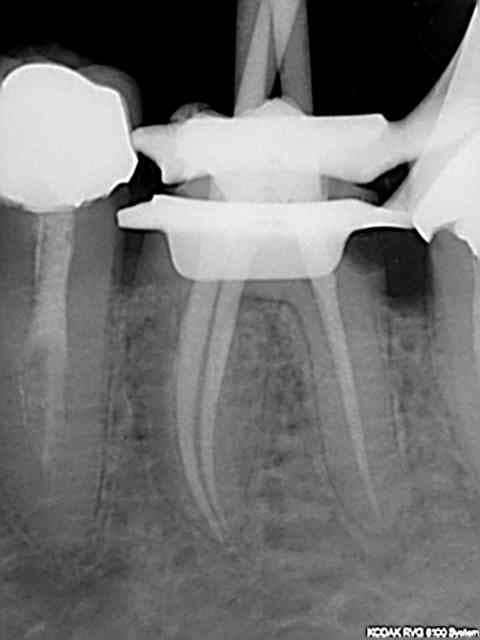

Oui, meme les handicapés psychomoteurs issus du concours font des pulpec molaires en 30 mn avec les réciproc r25.

La nomenclature a aussi beaucoup changé en 30 ans a tel point que je suis complètement largué avec ces histoires de Z6 + Z3+ Z3 Je ne sais pas coter ces radios la radio de départ (dite de diagnostic) faisant partie d'un status pris un autre jour mais sur lequel j'avais coté la 47 et la 44 mais pas la 46.))))))